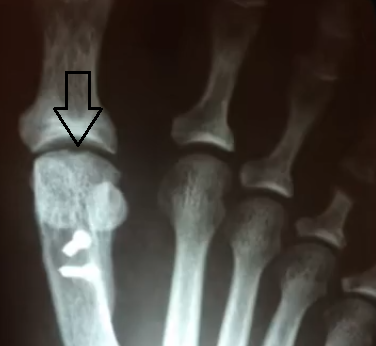

• Depressão no domo da cabeça do 1° metatarso (artrose inicial)

• Artrose na art. mtfl

• Osteófito dorsal na cabeça do 1° mtt